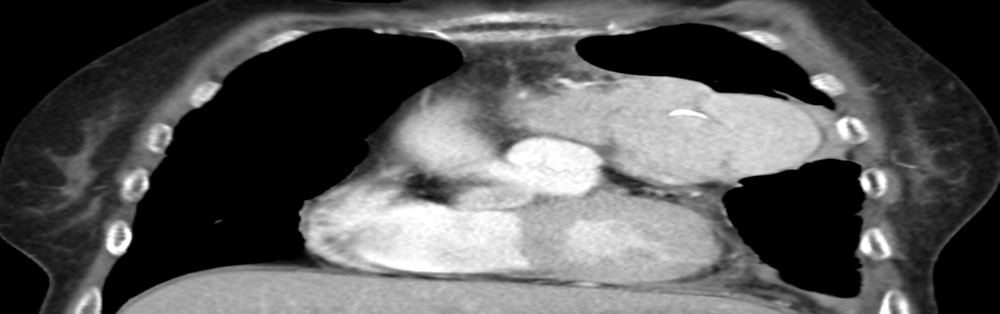

11月6日由胸外科闫天生主任主刀,王通主治医师、金亮住院医师做助手,为患者实施手术。手术先行VATS辅助下左侧胸腔探查,见肿物与心包及左肺动脉干、左肺上叶侵犯粘连,约6*9*12cm大小,分叶状。再沿左侧乳房下缘作弧形小切口,见肿瘤与心包、肺动脉、膈神经粘连极重,分界不清。逐层分离粘连,保护心包、肺动脉及膈神经,成功将肿物完整切除。手术历经3小时,出血仅仅30ml。